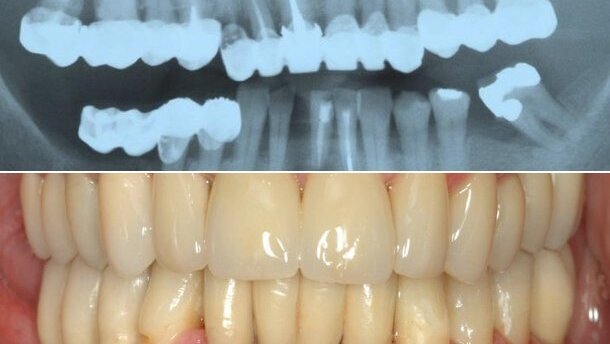

В уебинара лекторът – проф. Никлаус П. Ланг, ще представи на аудиторията установения процес по планиране на комплексен клиничен случай с помощта на добре развита структура и иновативен инструмент за лечебно планиране на образователната платформа Dental Campus. Представеният комплексен случай ще разгледа различните клинични аспекти на костната и мекотъканната регенерация и поставянето на импланти, а също така и протетичните аспекти и избора на материал.

Преминаването от аналогово към дигитално изработване на зъбни протези има ...